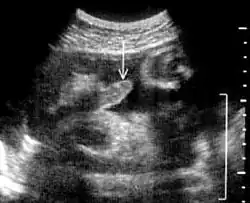

Oft wird die männliche Erektionsfähigkeit aus laienhafter Sichtweise der allgemeinen Manneskraft, Potenz oder Reproduktionsfähigkeit gleichgestellt und als Zeichen von Jugend und Vitalität betrachtet. Doch zu Erektionen kann es auch beim Fetus[1][2][3], bei Säuglingen[4][5] und Greisen kommen. Erektionen treten bei gesunden Menschen in nahezu jedem Lebensalter regelmäßig während des Schlafes innerhalb der so genannten REM-Phasen auf. Besteht eine solche beim Erwachen, wird sie morgendliche Erektion genannt. Auch Orgasmen mit Samenergüssen während des Schlafes, Pollutionen, sind sehr oft, aber nicht immer mit Erektionen verbunden.[6]

- ↑ D. M. Sherer, P. C. Eggers, J. R. Woods Jr.: In-utero fetal penile erection. In: Journal of Ultrasound in Medicine. (JUM), Juni 1990, Band 9, Nr. 6, S. 371, PMID 2192091.

- ↑ D. A. L. Pedreira, A. Yamasaki, C. E. Czeresnia: Fetal phallus ‘erection’ interfering with the sonographic determination of fetal gender in the first trimester. In: Ultrasound in Obstetrics & Gynecology. Okt. 2001, Band 18, Nr. 4, S. 402–404, doi:10.1046/j.0960-7692.2001.00532.x (Volltext).

- ↑ A. A. Jakobovits: Fetal penile erection. In: Ultrasound in Obstetrics & Gynecology. Oktober 2001, Band 18, Nr. 4, S. 405; doi:10.1046/j.0960-7692.2001.00477.x